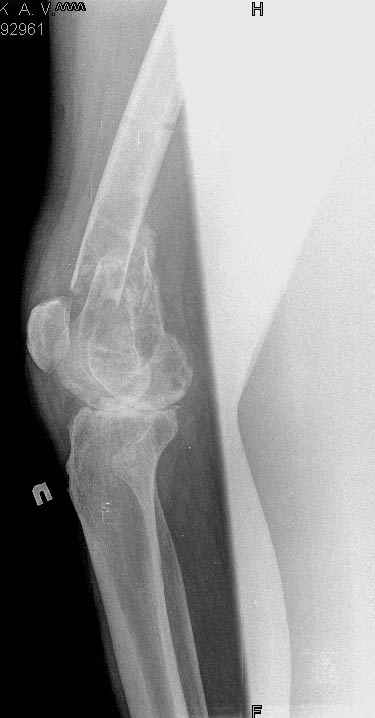

Коллеги!Окажите, пожалуйста, консультативную помощь.Мужчина, 41 год, 15 лет состоит на учете по поводу ревматоидного полиартрита, гормонзависимый (преднизолон получает нерегулярно). В процесс вовлечены крупные и мелкие суставы. 01.01.06 - без травмы наступил патологический перелом на границе н/3-с/3 бедра (перелом на фоне кистозных изменений?)

На рентгенограммах, помимо перелома, кистозные изменения на мыщелках б/берцовой кости и мыщелке бедра с другой стороны.